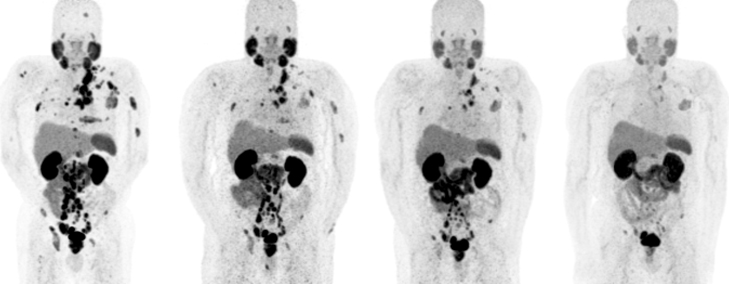

Lutetium-177 PSMA (abbreviated as 177Lu-PSMA therapy) is a form of radionuclide therapy currently being used in patients with prostate cancer.

A small quantity of PSMA (prostate specific membrane antigen) targeting molecule (for eg. PSMA-617, PSMA-I&T etc.) are attached to radioactive Lutetium-177. The PSMA targeting molecule targets the radiation of 177Lu to the prostate cancer target sites. The delivered radiation then kills the cancer cells

PSMA therapy is currently used in patients with metastatic prostate cancer (patients in whom the cancer has spread out of the prostate)